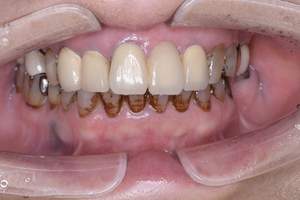

治療前

治療後

| 年齢 | 23歳・女性 |

|---|---|

| 主訴 | 着色取りたい |

| 治療内容 | エアフローで着色取り |

| 費用 | 5,500円(税込) (2024年07月現在) |

| 治療期間 | 1日 |

| リスク・副作用 | ナトリウムパウダーによるお口の不快感を伴うことがあります(うがいしていただくことで気にならない程度です)。 ケースにより完全に汚れを落としきれない場合があります。 歯ぐきの腫れや歯肉炎のある方は、ナトリウムパウダーがあたることにより、まれに痛みや出血をともなうことがあります。多くの場合、すぐに出血はおさまり、1~2日程度で歯ぐきは治癒していきます。 着色汚れはクリーニング後に再付着することがあります。定期的な受診をおすすめいたします。 |